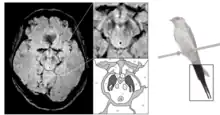

Le diagnostic de maladie de Parkinson est habituellement clinique. En théorie, la certitude du diagnostic n'est obtenue que par l'étude histologique du cerveau mais les critères diagnostiques actuellement définis permettent de faire le diagnostic sans trop de difficultés. Le scanner cérébral par tomodensitométrie des personnes atteintes de la maladie de Parkinson est habituellement normal[123]. L'imagerie par résonance magnétique sensible au fer (IRM T2*) peut être utilisée dans un cadre diagnostique. En effet, le fer peut être témoin de la mort cellulaire et le signal T2* diminue en présence de fer tandis que son inverse (R2*) augmente[124]. Dans la maladie de Parkinson, il existe une concentration en fer trop importante par rapport à la moyenne pour le même groupe d'âge au sein de la substance noire du fait de la perte de neurones dopaminergiques[125]. De plus, l'imagerie pondérée en fonction de la susceptibilité est elle aussi un marqueur fiable de la présence de fer intracérébral en étant à la fois sensible et spécifique à la maladie[126]. L'IRM T2* et l'imagerie pondérée en fonction de la susceptibilité sont toutes deux capables d'afficher le signe d'effacement de la queue d'hirondelle (swallow tail) dans la substance noire dorsolatérale. La tomodensitométrie et l'IRM sont également utilisées, en pratique clinique, pour écarter d'autres maladies pouvant engendrer un syndrome parkinsonien telles que l'encéphalite, les AVC chroniques, les tumeurs des ganglions de la base et l'hydrocéphalie[123].

Le Dat-scan est un type de scintigraphie cérébrale qui consiste à tracer les transporteurs de la dopamine de manière à pouvoir observer son parcours dans le cerveau. En effet, la tomographie par émission de positons (TEP) permet d'afficher l'activité métabolique des transporteurs dopaminergiques dans les ganglions de la base. Or, dans la maladie de Parkinson, on sait qu'il existe une mort pré-synaptique et les transporteurs de la dopamine disparaissent donc, le DaTSCAN est donc indiqué pour détecter la perte fonctionnelle des neurones dopaminergiques. Cette scintigraphie cérébrale (DaTSCAN) permettrait de montrer l'atteinte du striatum[127]. Un DaTSCAN est considéré comme normal si l'on peut observer une activité dopaminergique symétrique au sein des deux putamens des striatums, mais en cas d'asymétrie l'hypofixation dopaminergique est susceptible de dénoter une maladie de Parkinson. Le DaTSCAN corrèle bien avec le diagnostic clinique de la maladie de Parkinson[128]. De plus, une activité liée à la dopamine dans les ganglions de la base peut permettre d'exclure le syndrome parkinsonien iatrogène[123]. Une des premières indications du DaTSCAN fut de permettre la différenciation entre les tremblements essentiels des tremblements non essentiels (« parkinsoniens »)[129] et il dispose également également d'une AMM pour faire la distinction entre une démence due à la maladie d'Alzheimer ou une due à la démence à corps de Lewy. Toutefois, il faut noter que le DaTSCAN est incapble de différencier une démence associée à la maladie de Parkinson et une démence à corps de Lewy.